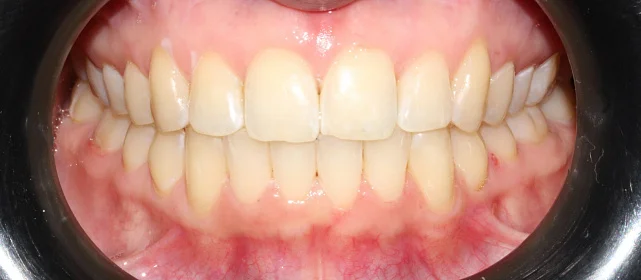

Нарушение соотношения челюстей и неправильное положение зубов — зубные ряды смыкались некорректно, зубы стояли со смещением.

Зубы выровнены, смыкание нормализовано. Установлены несъёмные ретейнеры на обе челюсти, сняты сканы для ретенционных кап. Консультация ортопеда запланирована на более поздний срок.

Проблема: Пациентку беспокоило неправильное смыкание зубов и их положение — ряды не сходились как нужно, зубы стояли со смещением. Это влияло и на внешний вид, и на то, как распределялась нагрузка при жевании.

Решение: Поставили прозрачные элайнеры 3D Smile на обе челюсти. Начали с набора из 34 кап, но в процессе стало понятно, что для полной коррекции нужна доработка — заказали дополнительный набор из 28 кап. Это нормальная ситуация: организм реагирует на перемещение зубов индивидуально, и заранее предсказать точное количество кап до последней штуки невозможно. В итоге 62 капы за 32 месяца — зубы встали на место, смыкание пришло в норму. Параллельно следили за гигиеной, чтобы дёсны оставались здоровыми на протяжении всего лечения.